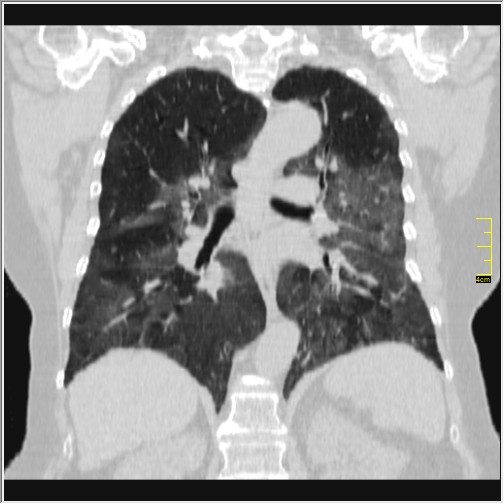

Foto: Aleksandar Ivković Foto: Aleksandar Ivković Foto: Aleksandar Ivković Strašna razlika kod pluća pušača i kovid pozitivne osobe autor: Božica Luković Zdravlje 23. jan. 2021. 12:06 > 23. jan. 2021. 12:15 0 Podeli vest: Radiolog Aleksandar Ivković od početka pandemije daje korisne informacije o svim aspektima kovida 19. On je nedavno uporedio rendgen snimke pluća zdrave osobe, pušača, osobe koja je zaražena gripom H1N1, a onda i osobe koja ima kovid 19. Razlike su zapanjujuće. Podeli vest: Oglas Objavu doktora Ivkovića sa njegovog bloga "Ljudi i ostale laži" prenosimo u celosti."Nedavno sam video u medijima da je neko preneo rdg sliku i razlike kod nalaza zdrave osobe, pušača i bolesnog od kovida 19. Kako nisam baš previše zadovoljan onim što je prikazano, evo kako to izgleda u našoj varijanti. Zdrava osoba CT nalaz kod zdrave osobe podrazumeva da ne postoje nikakvi poremećaji strukture plućnog parenhima, da su krvni sudovi uredni i da nema suženja disajnih puteva, kao i da nema uvećanih limfnih žlezda u hilusima pluća i medijastinumu. Foto: Aleksandar Ivković | Foto: Aleksandar Ivković * Foto: Aleksandar Ivković | Foto: Aleksandar Ivković Zdrava muška osoba mesec dana nakon zapaljenja pluća tokom kovida 19. Nalaz bez nekih posebnih problema iako se naziru tragovi zapaljenja. Snimak u boji je zdrava osoba, nepušač, bez ikakvih bolesti pluća u istoriji. Grip H1N1 Pokazaću samo drastične nalaze kod gripa H1N1, to je znači onaj grip koji je izazvao epidemiju španske groznice i epidemiju 2009. godine koja još uvek nije prestala (svake godine imamo makar 15%). Foto: Aleksandar Ivković | Foto: Aleksandar Ivković * Foto: Aleksandar Ivković | Foto: Aleksandar Ivković * Foto: Aleksandar Ivković | Foto: Aleksandar Ivković * Foto: Aleksandar Ivković | Foto: Aleksandar Ivković Nisu svi pacijenti imali ovakve nalaze, pokazujem one koji su imali tešku kliničku sliku. Kod gripa se sve odvija obično u sedam dana. Kao što se vidi, zapaljenje je bilo jednostrano, uglavnom. Ali kada je dolazilo do pogoršanja, onda je centralno obostrano dolazilo do edema pluća. Pušenje Kod pušača postoje razne varijante nalaza na plućima. U principu nisu tako dramatične kao što su zapaljenja. Nalaz na plućima kod pušača može biti potpuno normalan. Ovo ne pišem zato što podržavam pušenje, naprotiv, veliki sam protivnik, ali iznošenje laži nikada nije dobro. Dve dijagnoze su bitne kao posledica pušenja. Prva je hronična plućna opstruktivna bolest: Foto: Aleksandar Ivković | Foto: Aleksandar Ivković * Foto: Aleksandar Ivković | Foto: Aleksandar Ivković * Foto: Aleksandar Ivković | Foto: Aleksandar Ivković Jasna je razlika u nalazu, posebno na ovim slikama u boji, gde su ta plava polja delovi pluća koji su propali zbog cigareta (može da se uporedi sa zdravim plućima iznad).Druga bolest koja je česta kod pušača je u svakom slučaju karcinom. Foto: Aleksandar Ivković | Foto: Aleksandar Ivković * Foto: Aleksandar Ivković | Foto: Aleksandar Ivković * Foto: Aleksandar Ivković | Foto: Aleksandar Ivković * Foto: Aleksandar Ivković | Foto: Aleksandar Ivković Tkivo koje raste unutar pluća i razjeda ga. Takav je nalaz kod karcinoma pluća. Često je uzrok upotreba cigareta. Kovid 19 O kovidu sam pisao puno puta. Evo nekih slika, radi poređenja. Foto: Aleksandar Ivković | Foto: Aleksandar Ivković * Foto: Aleksandar Ivković | Foto: Aleksandar Ivković * Foto: Aleksandar Ivković | Foto: Aleksandar Ivković * Foto: Aleksandar Ivković | Foto: Aleksandar Ivković Nakon što pacijent bude izlečen od gripa ili kovida 19, pluća se mogu vratiti u normalu.To je razlika u odnosu na posledice upotrebe cigareta. Ovi snimci nisu postavljeni da bi se poredile bolesti, već da bi se ukazalo kako različite bolesti deluju na pluća. I ono što je veoma važno, ako neko dobije jednu od ovih bolesti, ne znači da u toku života neće dobiti drugu.Ne pišem zato smo smatram da sam najpametniji ili najpozvaniji da objašnjavam, nisam kao neki pojedinci ubeđen da samo ja imam znanje i istinu, pišem jer drugi ćute. Pišem jer ima i puno onih koji iznose laži, mora se tome stati na put.A ovi, koji pišu da sam umro, da sam oboleo od karcinoma, ovi koji mi žele da nađem dobro grobno mesto, šta da vam kažem, vi ste mi inspiracija. Svesni ste da sam u pravu i odlično znam da ste već uradili sve da se vakcinišete i mnogi od vas će to uraditi pre mene ali i dalje ćete ubeđivati druge da se ne vakcinišu i da je dobro za njih da se razbole i umru. Ima puno reči za vas u svim našim slovenskim jezicima, znate vi sami šta ste", piše dr Ivković.***Bonus video:https://youtu.be/MWucTT0qBsIPratite nas i na društvenim mrežama:FacebookTwitterInstagram Dr Lukić otkrio spisak svih antibiotika za kovid upalu pluća Zdravlje 0 Dr Žujović: Kako oporaviti pluća posle korone Zdravlje 0 Pet znakova da ti je kovid zahvatio pluća Zdravlje 0 Virusolog Ana Banko ruši veliku zabludu o ruskoj vakcini Emisije 0 aleksandar ivković korona kovid pluća snimak pluća Pratite nas na društvenim mrežama: Koje je tvoje mišljenje o ovoj temi? Učestvuj u diskusiji ili pročitaj komentare Budite prvi koji će ostaviti komentar Pošalji komentar Pročitaj komentare (0)